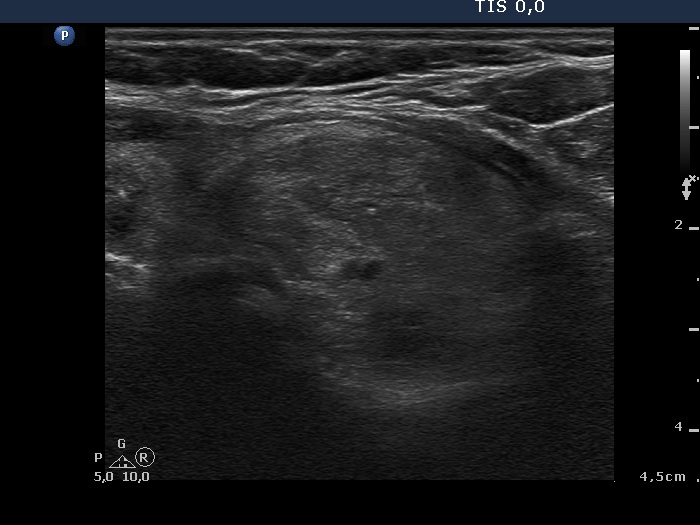

Study on 100 consecutive patients with thyroid nodule - case 014 (ultrasonographic picture 7)

Lower part of the left lobe, transverse view. Another moderately hypoechogenic nodule was found in the lower third of the lobe.